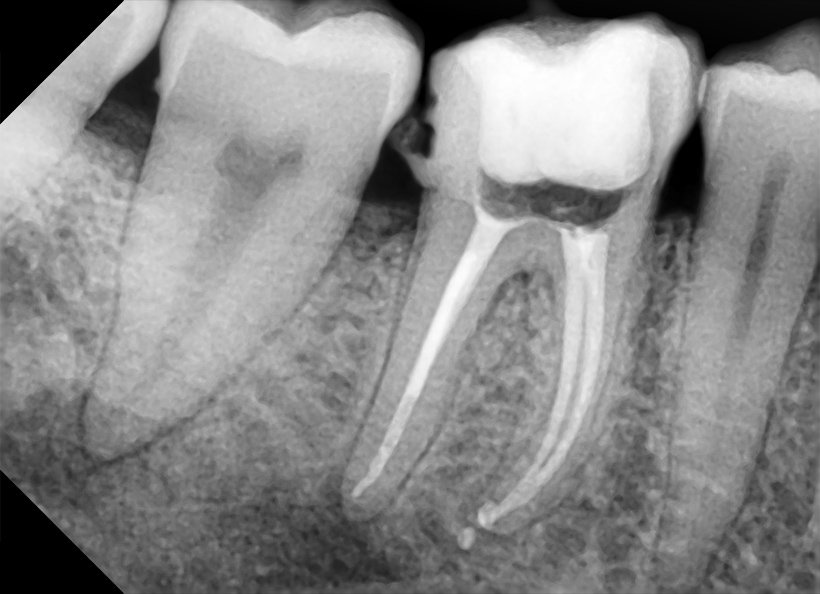

Radiografia digitală retroalveolară

Radiografia periapicală, cunoscută și sub denumirea de retroalveolară, este o investigație imagistică precisă, utilizată pentru a examina în detaliu un dinte sau un grup mic, de maximum doi-trei dinți. Aceasta surprinde întreaga structură a dintelui, la dimensiuni reale, incluzând coroana, rădăcina și osul alveolar în care dintele este fixat. Este o metodă indispensabilă în cadrul tratamentelor endodontice, parodontale sau chirurgicale, deoarece permite medicului stomatolog să evalueze cu acuratețe starea rădăcinii, a coroanei și a țesuturilor înconjurătoare. De asemenea, radiografia retroalveolară ajută la identificarea eventualelor afecțiuni, cum ar fi carii profunde, leziuni periapicale sau anomalii ale structurii dentare, contribuind astfel la un diagnostic corect și la planificarea unui tratament eficient.